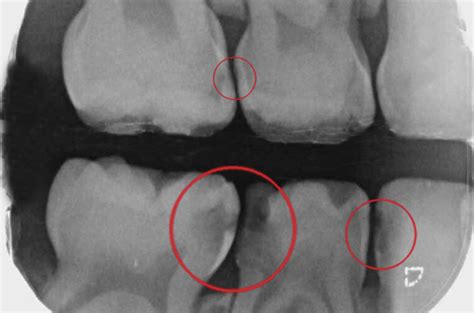

Es muy importante realizar revisiones periódicas en el dentista para poder detectar las caries interproximales de forma precoz. Será el especialista quien, mediante una radiografía, pueda hacer un diagnóstico y aplicar el tratamiento para las caries interproximales más adecuado. Una forma de detectar la caries interproximal es cuando, al pasar el hilo dental, notamos que se engancha y provoca dolor.

La caries interproximal es aquella que se desarrolla en los espacios entre los dientes. Estas caries son más difíciles de detectar y, al afectar a más de un diente, son especialmente graves. Las personas con apiñamiento de dientes o que llevan ortodoncia o prótesis tienen más riesgo de padecer caries interproximales porque son más propensas a la acumulación de alimentos.

Las caries interdentales, también conocidas como caries interproximales, son aquellas que se desarrollan en los espacios entre los dientes, donde el cepillo dental no llega con facilidad. Estas caries se forman debido a la acumulación de placa bacteriana en zonas de difícil acceso.